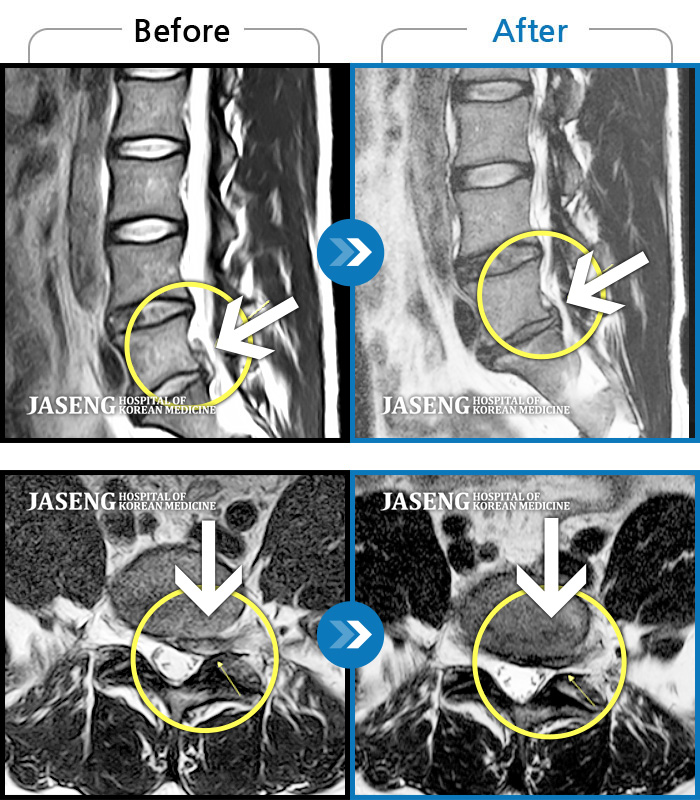

MRI 치료사례

허리통증, 왼쪽 다리 통증 및 근력 저하